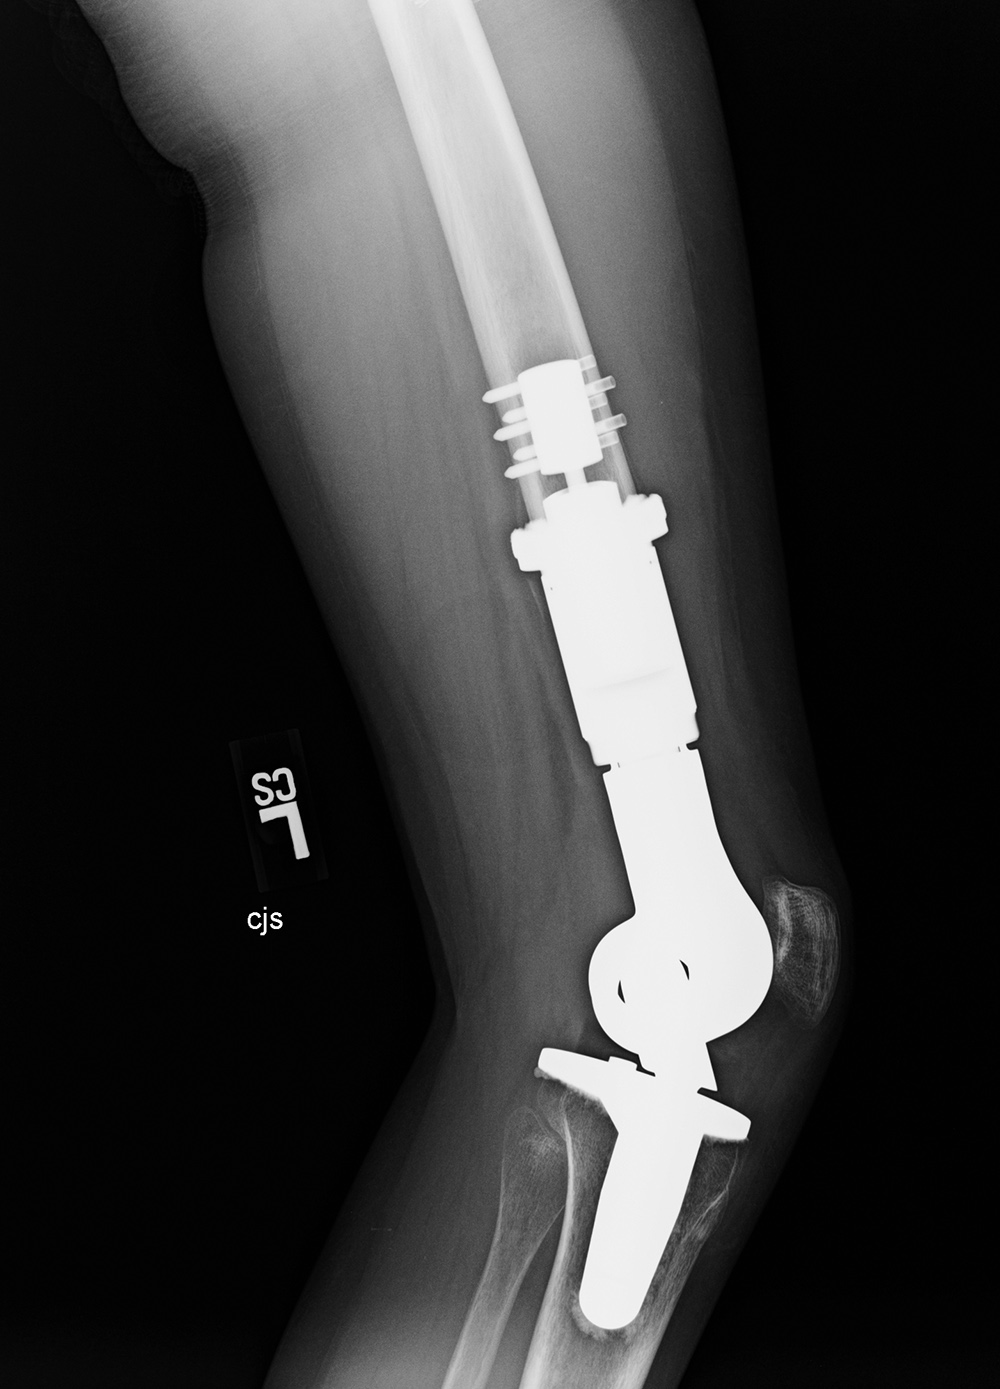

Limb sparing (salvage) prosthesis Varus-valgus lower limb salvage prosthesis (limb-salvage total knee arthroplasty)

Limb sparing prosthesis Limb sparing prosthesis lateral view Lower limb salvage prosthesis Lower limb salvage prosthesis

17 year-old woman with Ewing sarcoma treated with limb sparing prosthesis This is a custom made prosthesis for a patient who was treated for a Ewing sarcoma. From Taljanovic, 2005